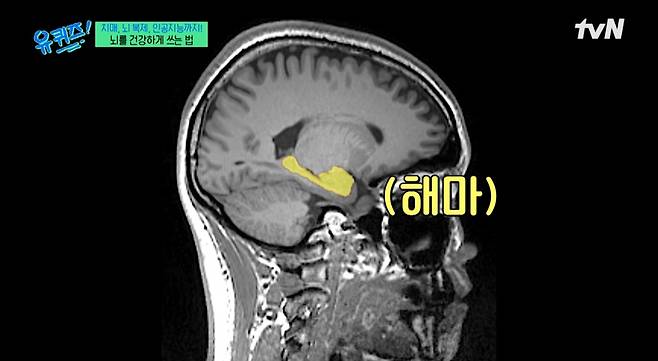

이인아 뇌인지과학과 교수가 해마에 관해 설명했다.

이날 유재석은 “해마 연구 권위자”라며 뇌에 대해 연구하는 이인아 교수를 소개했다. 이 교수는 “해마는 벌어진 일을 한 번만 벌어져도 다 기억한다. 평생 쌓이면 엄청난 양의 기억이 되는 것”이라며 기억을 토대로 앞날을 예측, 대비하는 역할을 한다고 설명했다.

또한, 그는 “해마는 단순히 과거의 기억을 저장하는 영역은 아니고 과거 기억을 교훈 삼아 미래를 대비하기 위한 영역”이라고 전했다. 이어 “기억은 미래를 위한 것이다. 과거를 붙잡기 위한 게 아니고”라고 덧붙여 눈길을 끌었다. 이 교수는 “해마가 손상되면 새로운 사건이 벌어져도 기록이 안 된다. 계속 찰나에 사는 것”이라고 말했다.